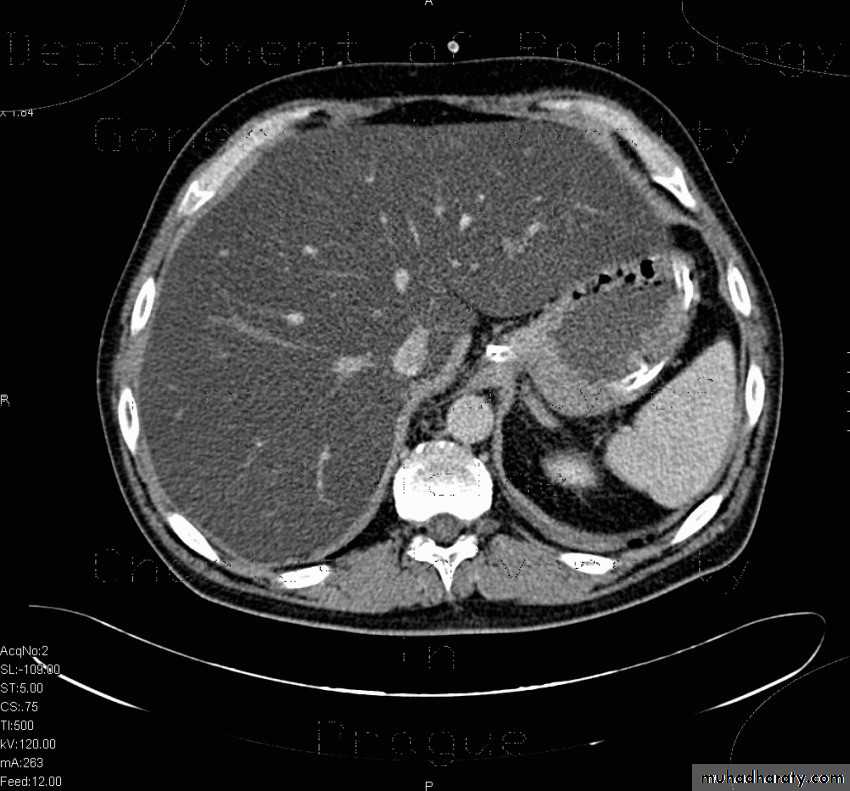

Benign lesions

Hemangioma